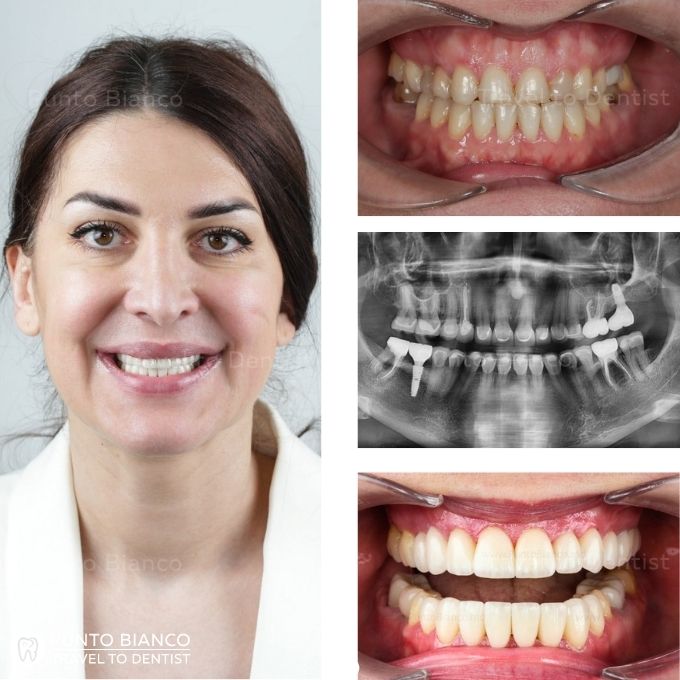

Reabilitare dentară estetică și funcțională completă

Problema

Pacienta din România stabilită în Elveția, a venit la clinica Punto Bianco cu tratament de ortodonție facut în altă clinică și trebuia continuat cu fațete, pacienta avea gingivită cronică generalizată.

Soluția

S-au tratat cariile și s-au retratat canalele acolo unde a fost necesar, s-au inserat implanturile dentare premium în zona edentată după care s-au aplicat fațetele ceramice Emax și coroane din zirconiu, s-au stabilit și s-au protejat dinții pe termen lung prin gutiră pentru bruxism.

Durata

10 zile prima etapă după 6 luni pacienta a revenit pentru imbolizarea dinților și după alte 6 luni s-au fixat coroanele.